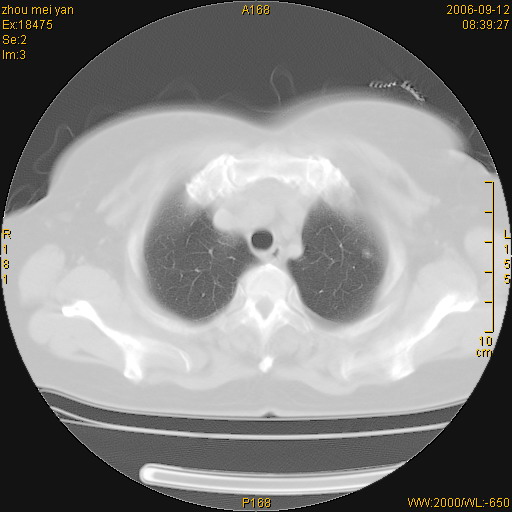

患者、女、55岁。因心率失常住院检查ct发现胸部多发结节。腹部b超肝、胆、胰、脾、肾、子宫附件未见异常。无结核病史,无粉尘接触史。请大家来会诊。谢谢!

影像表现十分有特点:双侧肋胸膜及膈胸膜广泛散在分布大小在2至6mm左右,较大病灶中心可见钙化。

感染性肉芽肿,双侧膈底胸膜见多个结节灶,内见斑点状钙化,有否疫水接触史

双侧肋胸膜及膈胸膜广泛散在分布大小不等结节影,较大病灶中心可见钙化。